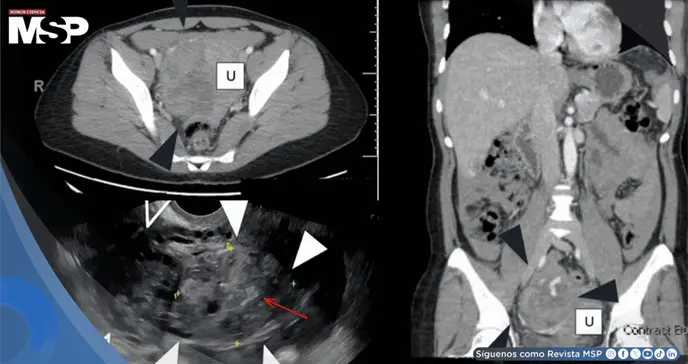

La ecografía transvaginal detectó una masa sólida de 5 cm en el ovario derecho, ascitis en pelvis y abdomen, más líquido simple en fondo de saco y anexos derechos, sin embarazo intrauterino visible.

Los niveles de ßHCG subieron levemente de 260 a 301 mUI/ml en 48 horas. La tomografía computarizada (TC) agravó la sospecha: masa anexial heterogénea de 8,8 cm con vascularidad periférica y líquido libre hiperdenso, evocando posible malignidad ovárica. Marcadores tumorales como CEA y CA-125 resultaron normales.

La ecografía mostró masa sólida vascularizada sin "anillo de fuego" clásico, rodeada de corteza ovárica con folículos. La TC reveló heterogeneidad y hemoperitoneo, hallazgos compartidos con quistes hemorrágicos rotos o tumores. Líquido libre pélvico es inespecífico, y tejido trofoblástico puede inducir vasos anormales, simulando neoplasias.